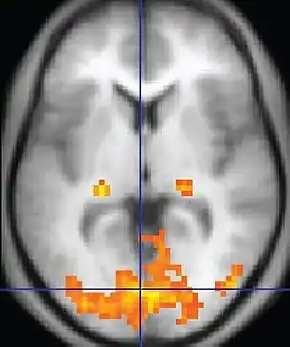

![]() An fMRI image with yellow areas showing increased activity compared with a control condition | |

Functional magnetic resonance imaging or functional MRI (fMRI) measures brain activity by detecting changes associated with blood flow.[1][2] This technique relies on the fact that cerebral blood flow and neuronal activation are coupled. When an area of the brain is in use, blood flow to that region also increases.[3]

The primary form of fMRI uses the blood-oxygen-level dependent (BOLD) contrast,[4] discovered by Seiji Ogawa in 1990. This is a type of specialized brain and body scan used to map neural activity in the brain or spinal cord of humans or other animals by imaging the change in blood flow (hemodynamic response) related to energy use by brain cells.[4] Since the early 1990s, fMRI has come to dominate brain mapping research because it does not involve the use of injections, surgery, the ingestion of substances, or exposure to ionizing radiation.[5] This measure is frequently corrupted by noise from various sources; hence, statistical procedures are used to extract the underlying signal. The resulting brain activation can be graphically represented by color-coding the strength of activation across the brain or the specific region studied. The technique can localize activity to within millimeters but, using standard techniques, no better than within a window of a few seconds.[6] Other methods of obtaining contrast are arterial spin labeling[7] and diffusion MRI. Diffusion MRI is similar to BOLD fMRI but provides contrast based on the magnitude of diffusion of water molecules in the brain.